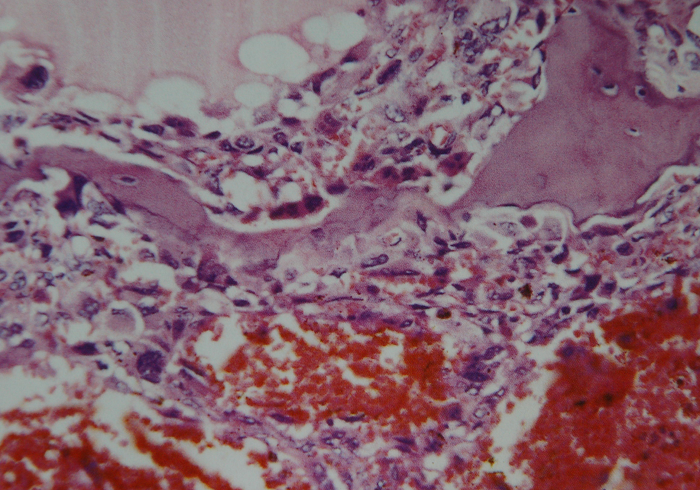

图 32 组织学特点:在扩张的血管间

见异型成骨细胞,正常的骨小梁

被破坏。